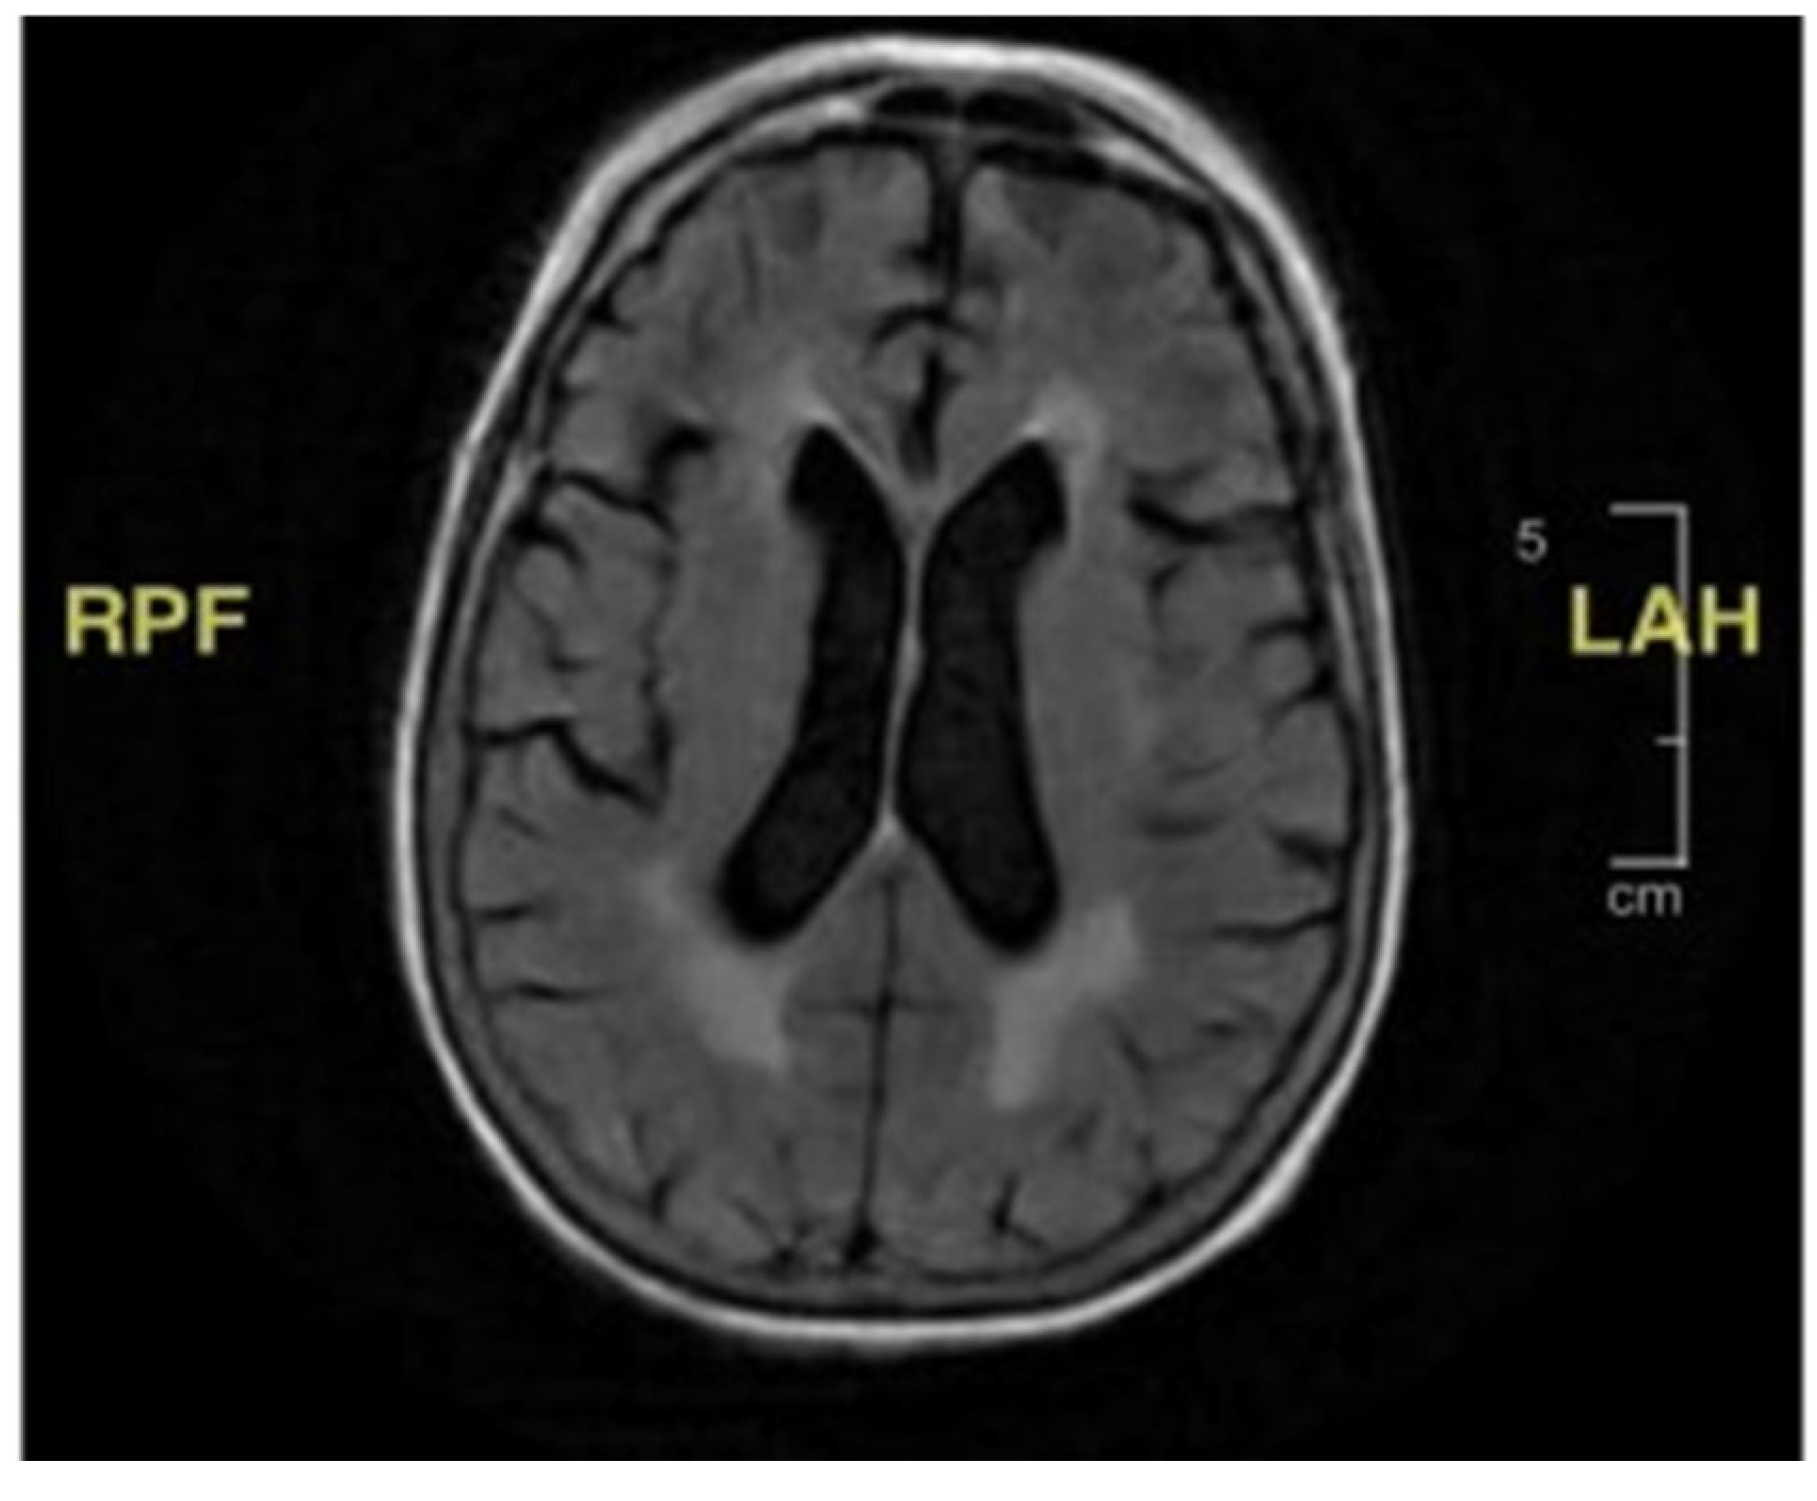

Her second hospital admission was precipitated by repeated ground-level falls from severe bilateral leg weakness. On this occasion, she described worsening back pain with ambulation. She also developed a left facial droop during the second admission. Extensive imaging, including another MRI and CT scan, showed no ischemic changes in the head and neck or acute stroke. Repeat cerebral MRI with and without contrast was negative (Figure 2). Lumbar spine MRI showed advanced degenerative disk disease but no significant pathology explaining her bilateral lower-extremity weakness (Figure 3). Lumbar spine CT showed moderate spinal stenosis at the two lowest vertebrae of the lumbar spine and a 2 mm anterolisthesis. The patient did not exhibit urinary or fecal incontinence.

During the third admission, she developed diarrhea with a one-week duration. Stool studies confirmed campylobacteriosis, which was treated with azithromycin. During this hospitalization, the patient once again developed a left-sided facial droop. Extensive imaging, including further head CT and CT angiography (CTA), showed no acute head and neck vascular ischemic changes. There were no spinal MRI findings (Figure 3) that could explain her lower-extremity weakness. During this admission, she underwent her first lumbar puncture, with the results displayed in Table 1. Ultimately, the patient was diagnosed with Bell’s palsy and completed 7 days of prednisone and 5 days of acyclovir. By this point, she had developed an immense fear of falling and was discharged to a rehabilitation facility for mobility and activities of daily living therapy.

Figure 3. Lumbar spine MRI without contrast. The bracket encloses the area where there appear to be degenerative changes, which are most pronounced at the lumbar vertebral levels of L3–L4 and L4–L5. There is also some degree of spinal canal stenosis, at least moderate at L3–L4. Based upon the MRI, there are no acute fractures or subluxation.